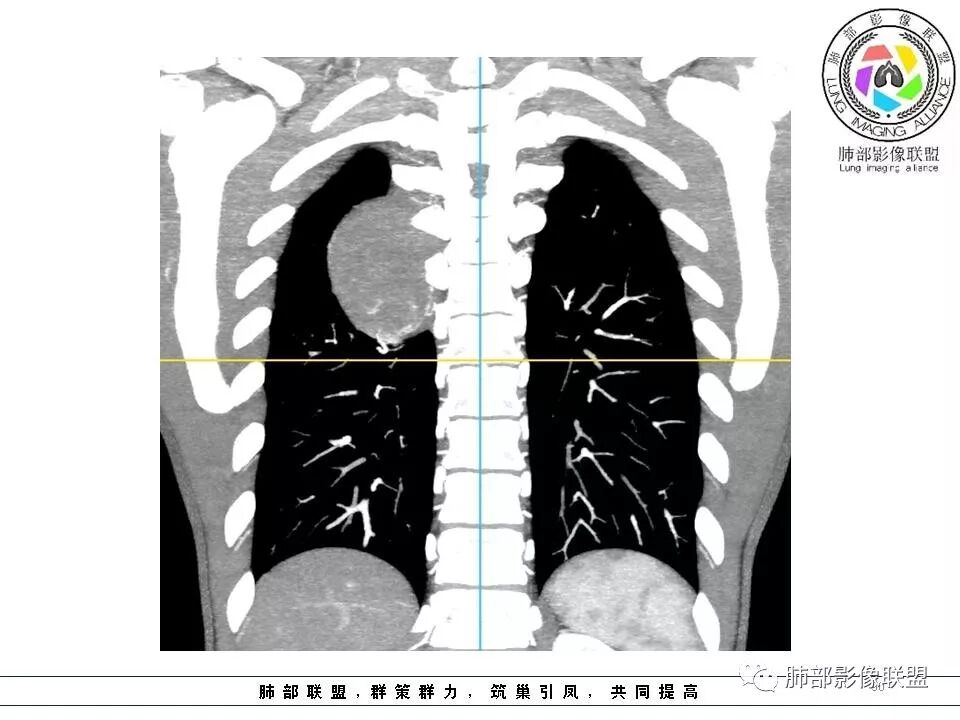

【每日晨读】脊柱旁肿瘤之争:您能一锤定音吗?

7.17晨读病例

病例

病例小结

1.右上胸内脊柱旁类圆形肿块,质地似乎比较坚实,密度稍显不均,但未显示明确的坏死。

如此密度形态的病灶位于肺边缘首先应当想到孤立性纤维瘤,可相邻胸膜未见明显的异常强化和胸膜方向延伸。

注意所谓“胸膜尾征”的概念及形成机制与“脑膜尾征”是大不相同的。

2.肋间动脉病供血也提示肿块来自后纵隔?

3.相邻椎间孔未见扩大,也未见块影延入椎管,易起自于神经根的鞘瘤似乎找不到支持点。

可惜未提供矢状位骨窗图像,如在肋骨内下缘观察到压迹有助于肋间神经的鞘瘤的判断,这是因为二者之间密切的毗邻关系。

4.静脉期轻度不均匀强化,注意不是环形强化,亦未见明确的“AB区”,这点也不支持神经鞘瘤。临床及病灶轻度强化都不支持副节瘤。

尽管神经纤维瘤的诊断确实有些出乎意外,但病例开阔了我们的视野。

未见多发病灶,患者有无脑内及皮肤病变,资料未能提供,稍显遗憾。